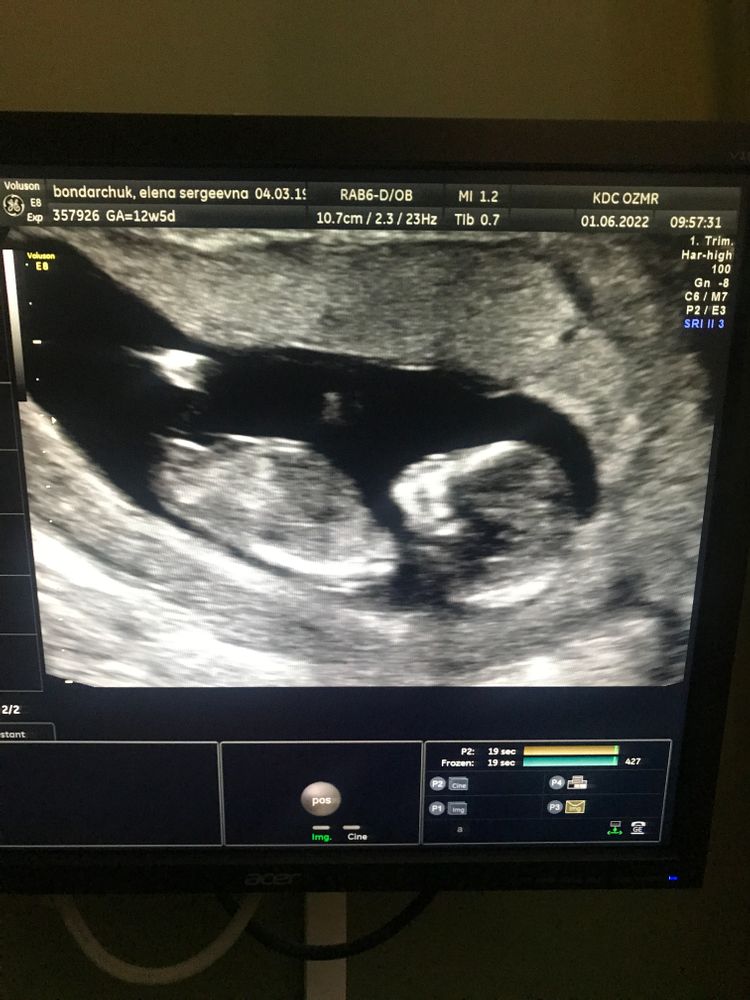

Поиграем в Вангу)))

Девочка. У моих мальчиков половой бугорок торчал под углом 90'

Matimacheha, честно я уже совсем наверное с ума сошла вчера ))) смотрела узи мальчиков и девочек в интернете)))) и сестра тоже сказала что у мальчиков идёт под своим углом, выше… конечно тут фото … специалист узи смотрит в движении, не всем предполагают на первом узи, я рада что если предположили значит малышка была не стеснительная на движение)) уже второе узи кстати убегает куда то постоянно 🤣🤣🤣

Мими, я когда смотрела на экран - смеялась и ревела одновременно… если честно не совсем доходит до конца что это у тебя под сердцем) особенно когда это первая беременность в 29 лет, к которой я долго шла) лежит там, что то ручкой по лицу трогает))) в такой момент когда врачи говорят что все супер все по срокам нет ни каких угроз и тд, кажется что даже Пофиг кто-там, лишь бы было все хорошо 🙏🏻 но конечно как большинству женщин мне бы хотелось дочку🤣 потому что я стилист/визажист, мне хочется в будущем делать причёски и макияж не только клиентам)))

Забыла отписаться всем "вангам"))) девочки, нам сейчас 23 недели, и это ДОЧКА!))) всем спасибо :*